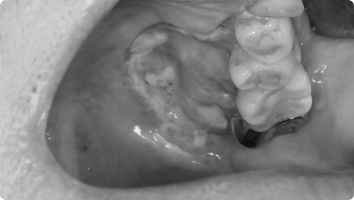

점액낭종은 입술이나 뺨 안쪽에 생기는 투명하거나 푸른빛의 물집 같은 혹입니다.

침샘이 다쳐서 침이 고이면서 발생하는 경우가 많습니다.

보통 통증은 없지만, 자꾸 커지거나 재발할 수 있습니다.

- 국소마취 후, 혹과 주변 침샘을 함께 절제하여 제거합니다.

- 크지 않고 안전한 수술로, 대부분 당일 바로 일상생활이 가능합니다.

- 재발 방지를 위해 병소를 확실하게 제거하는 것이 중요합니다.

하마종은 혀 밑에 생기는 큰 물집 같은 혹으로, 점액낭종이 큰 침샘(혀밑샘)과 연결되어 발생하는 경우가 많습니다.

커지면 말하거나 음식을 먹을 때 불편할 수 있습니다.

- 국소마취 후, 혹을 완전히 절제하기보다 조대술(구멍을 만들어 침이 빠지도록 하는 방법)을 시행합니다.

- 병소의 벽을 일부 열어주어 침이 고이지 않고 자연스럽게 배출되게 합니다.

- 수술 시간이 짧고, 회복도 빠른 편입니다.